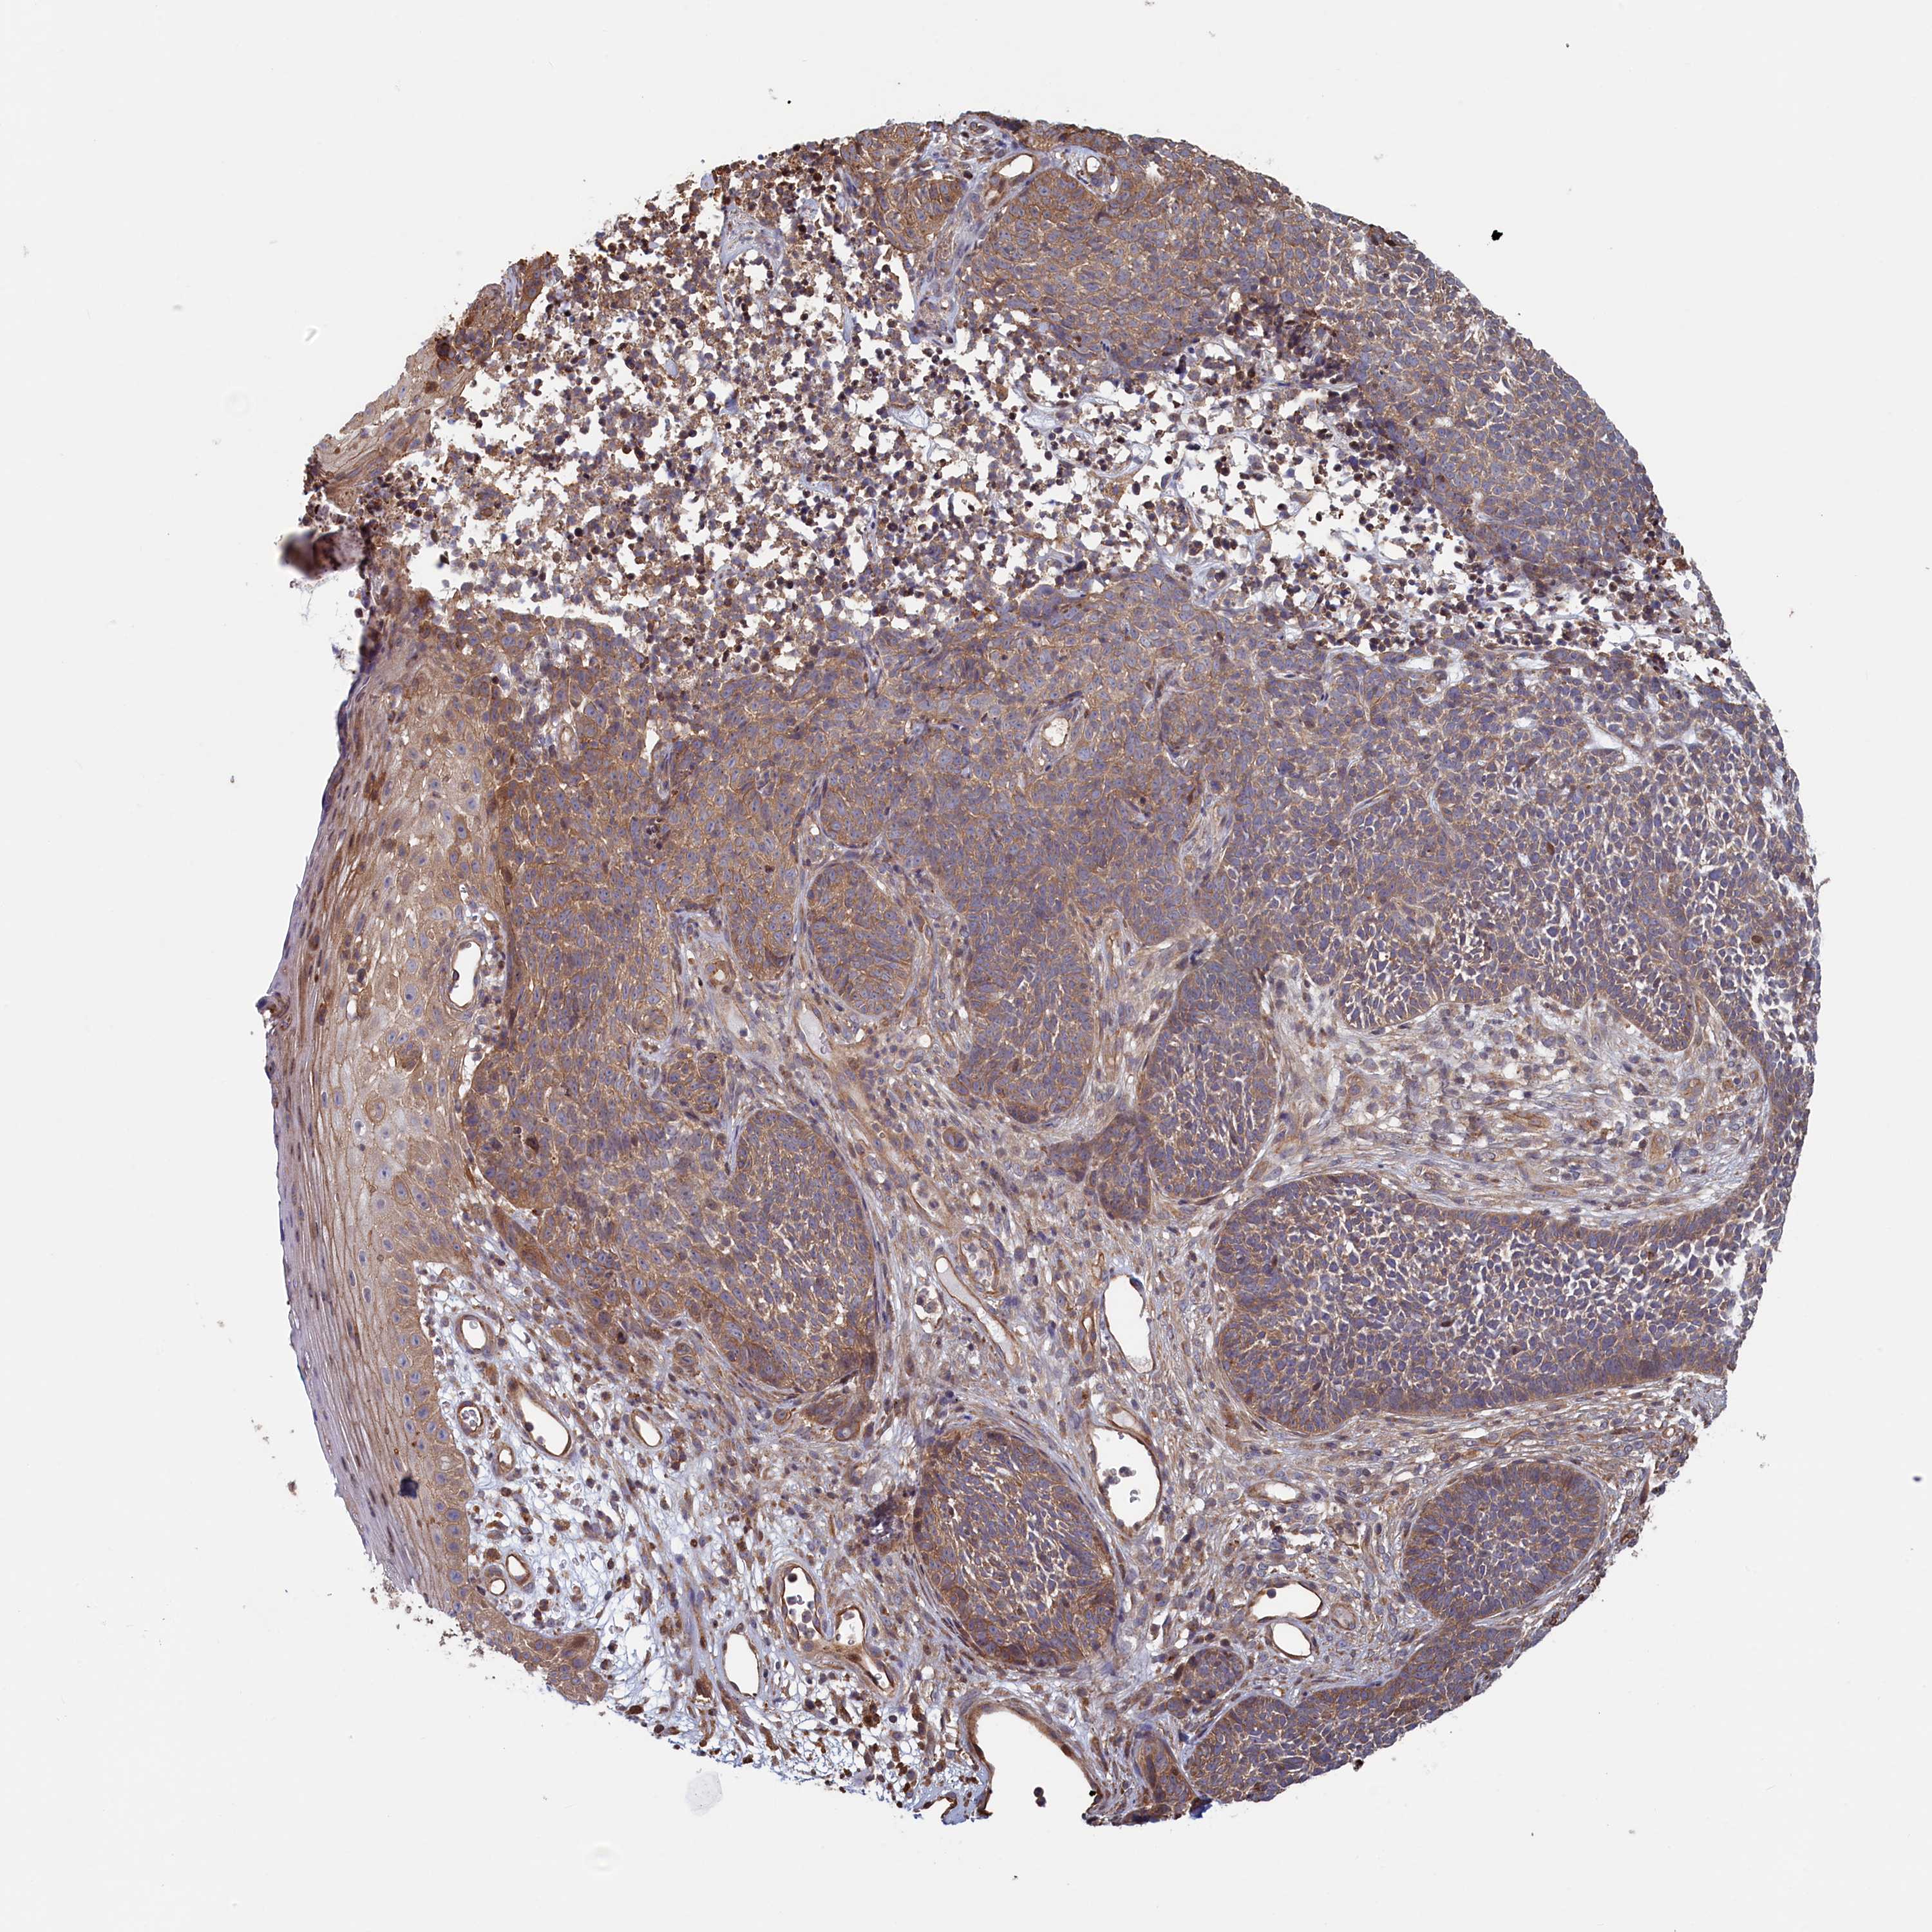

SKIN CANCER - Protein expressioni

A mouse-over function shows sample information and annotation data. Click on an image to view it in a full screen mode. Samples can be filtered based on level of antibody staining by selecting one or several of the following categories: high, medium, low and not detected. The assay and annotation is described here.

Antibody stainingi

Antibody staining in the annotated cell types in the current human tissue is reported as not detected, low, medium, or high, based on conventional immunohistochemistry profiling in selected tissues. This score is based on the combination of the staining intensity and fraction of stained cells.

Each image is clickable and will lead to virtual microscopy that enables deeper exploration of all samples and also displays staining intensity scores, fraction scores and subcellular localization as well as patient and tissue information for each sample.

Antibody HPA041314

Staining

High

Intensity

Strong

Quantity

>75%

Location

Nuclear

Basal cell carcinoma